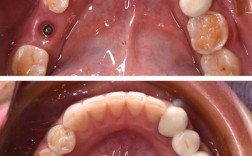

等了10天,我去试戴牙冠,医生拿出烤瓷牙冠,颜色跟我旁边的真牙几乎一样,透光性也挺好,把牙冠往基台上套,调整了几次咬合,确保不疼、不顶,确认合适后,用专门的粘接剂把牙冠固定在基台上,整个过程不到半小时,当镜子看到“新牙齿”的那一刻,真的太激动了!形状、颜色、光泽都跟真牙一样,完全看不出是种的。

刚戴上牙冠,医生说前几天要适应,别啃硬骨头、螃蟹壳、坚果,避免用门牙咬苹果(用后牙嚼就行),另外要注意清洁,每天用牙线剔牙缝,种植牙周围牙龈容易藏食物残渣,用软毛牙刷刷的时候,重点清洁牙龈边缘。